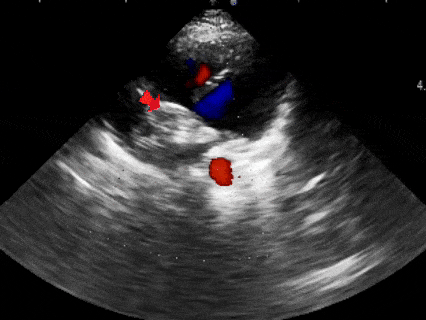

超声下观察封堵器,左右盘面在房间隔两侧,彩超下无残余分流

多普勒观察封堵器成型后无残余分流

多普勒观察无残余分流